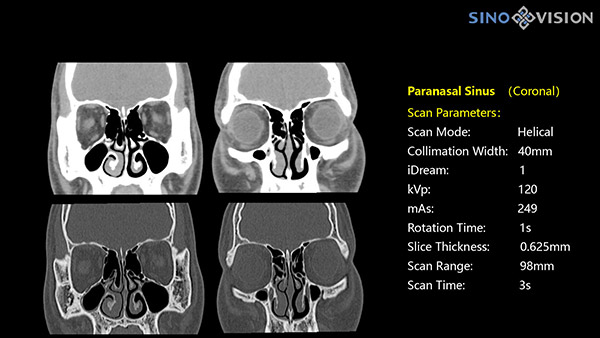

Инновационный 128-срезовый компьютерный томограф SinoVision InsitumCT 568 – это сочетание высокой скорости работы, низкой дозы и максимума возможностей для подавляющего большинства клинических случаев, как в рутинных, так и в углубленных специализированных исследованиях, в том числе педиатрические и кардиологические исследования при сверхнизких дозах.

Полнофункциональный 128-резовый компьютерный томограф InsitumCT 568 - это лучшее в новом поколении широкодиапазонных томографов с 128 срезами и большой диафрагмой. Этот КТ-сканер с большой апертурой обеспечивает 128 срезов КТ с диафрагмой 76 см, улучшает разрешение изображения до 21Lp/cm, помогает точно диагностировать и лечить заболевания, а также значительно улучшает клинические характеристики и расширяемость оборудования. Позволяет реализовать визуализацию в высоком разрешении и в малых дозах лучевой нагрузки.

- Толщина среза: 0.625 мм

Характеристики сканирования

- Минимальное время одного оборота рентгеновской трубки: От 0.48 до 2 сек